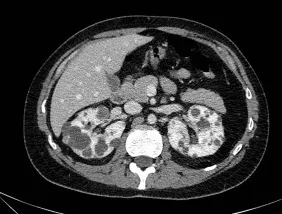

Injúria Renal Aguda (revisão Lancet 2025)